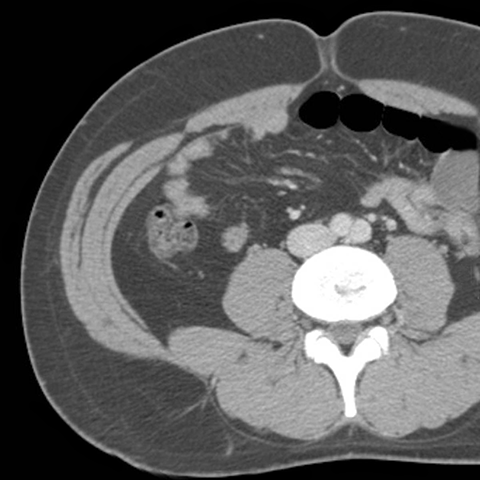

Abdominal Wall Muscles Normal Anatomy, Axial CT [5 of 9]